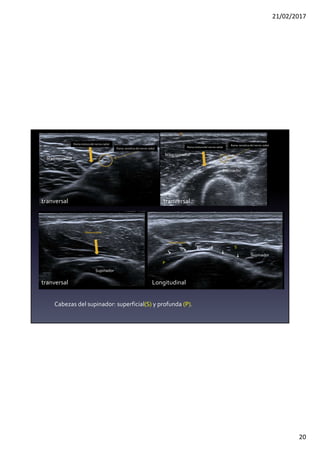

Rama motoradel nervio radial

Rama sensitiva del nervio radial

Supinador

S

P

Rama motora

Longitudinal

tranversal

braquiorradial

Cabezas del supinador: superficial(S) y profunda (P).